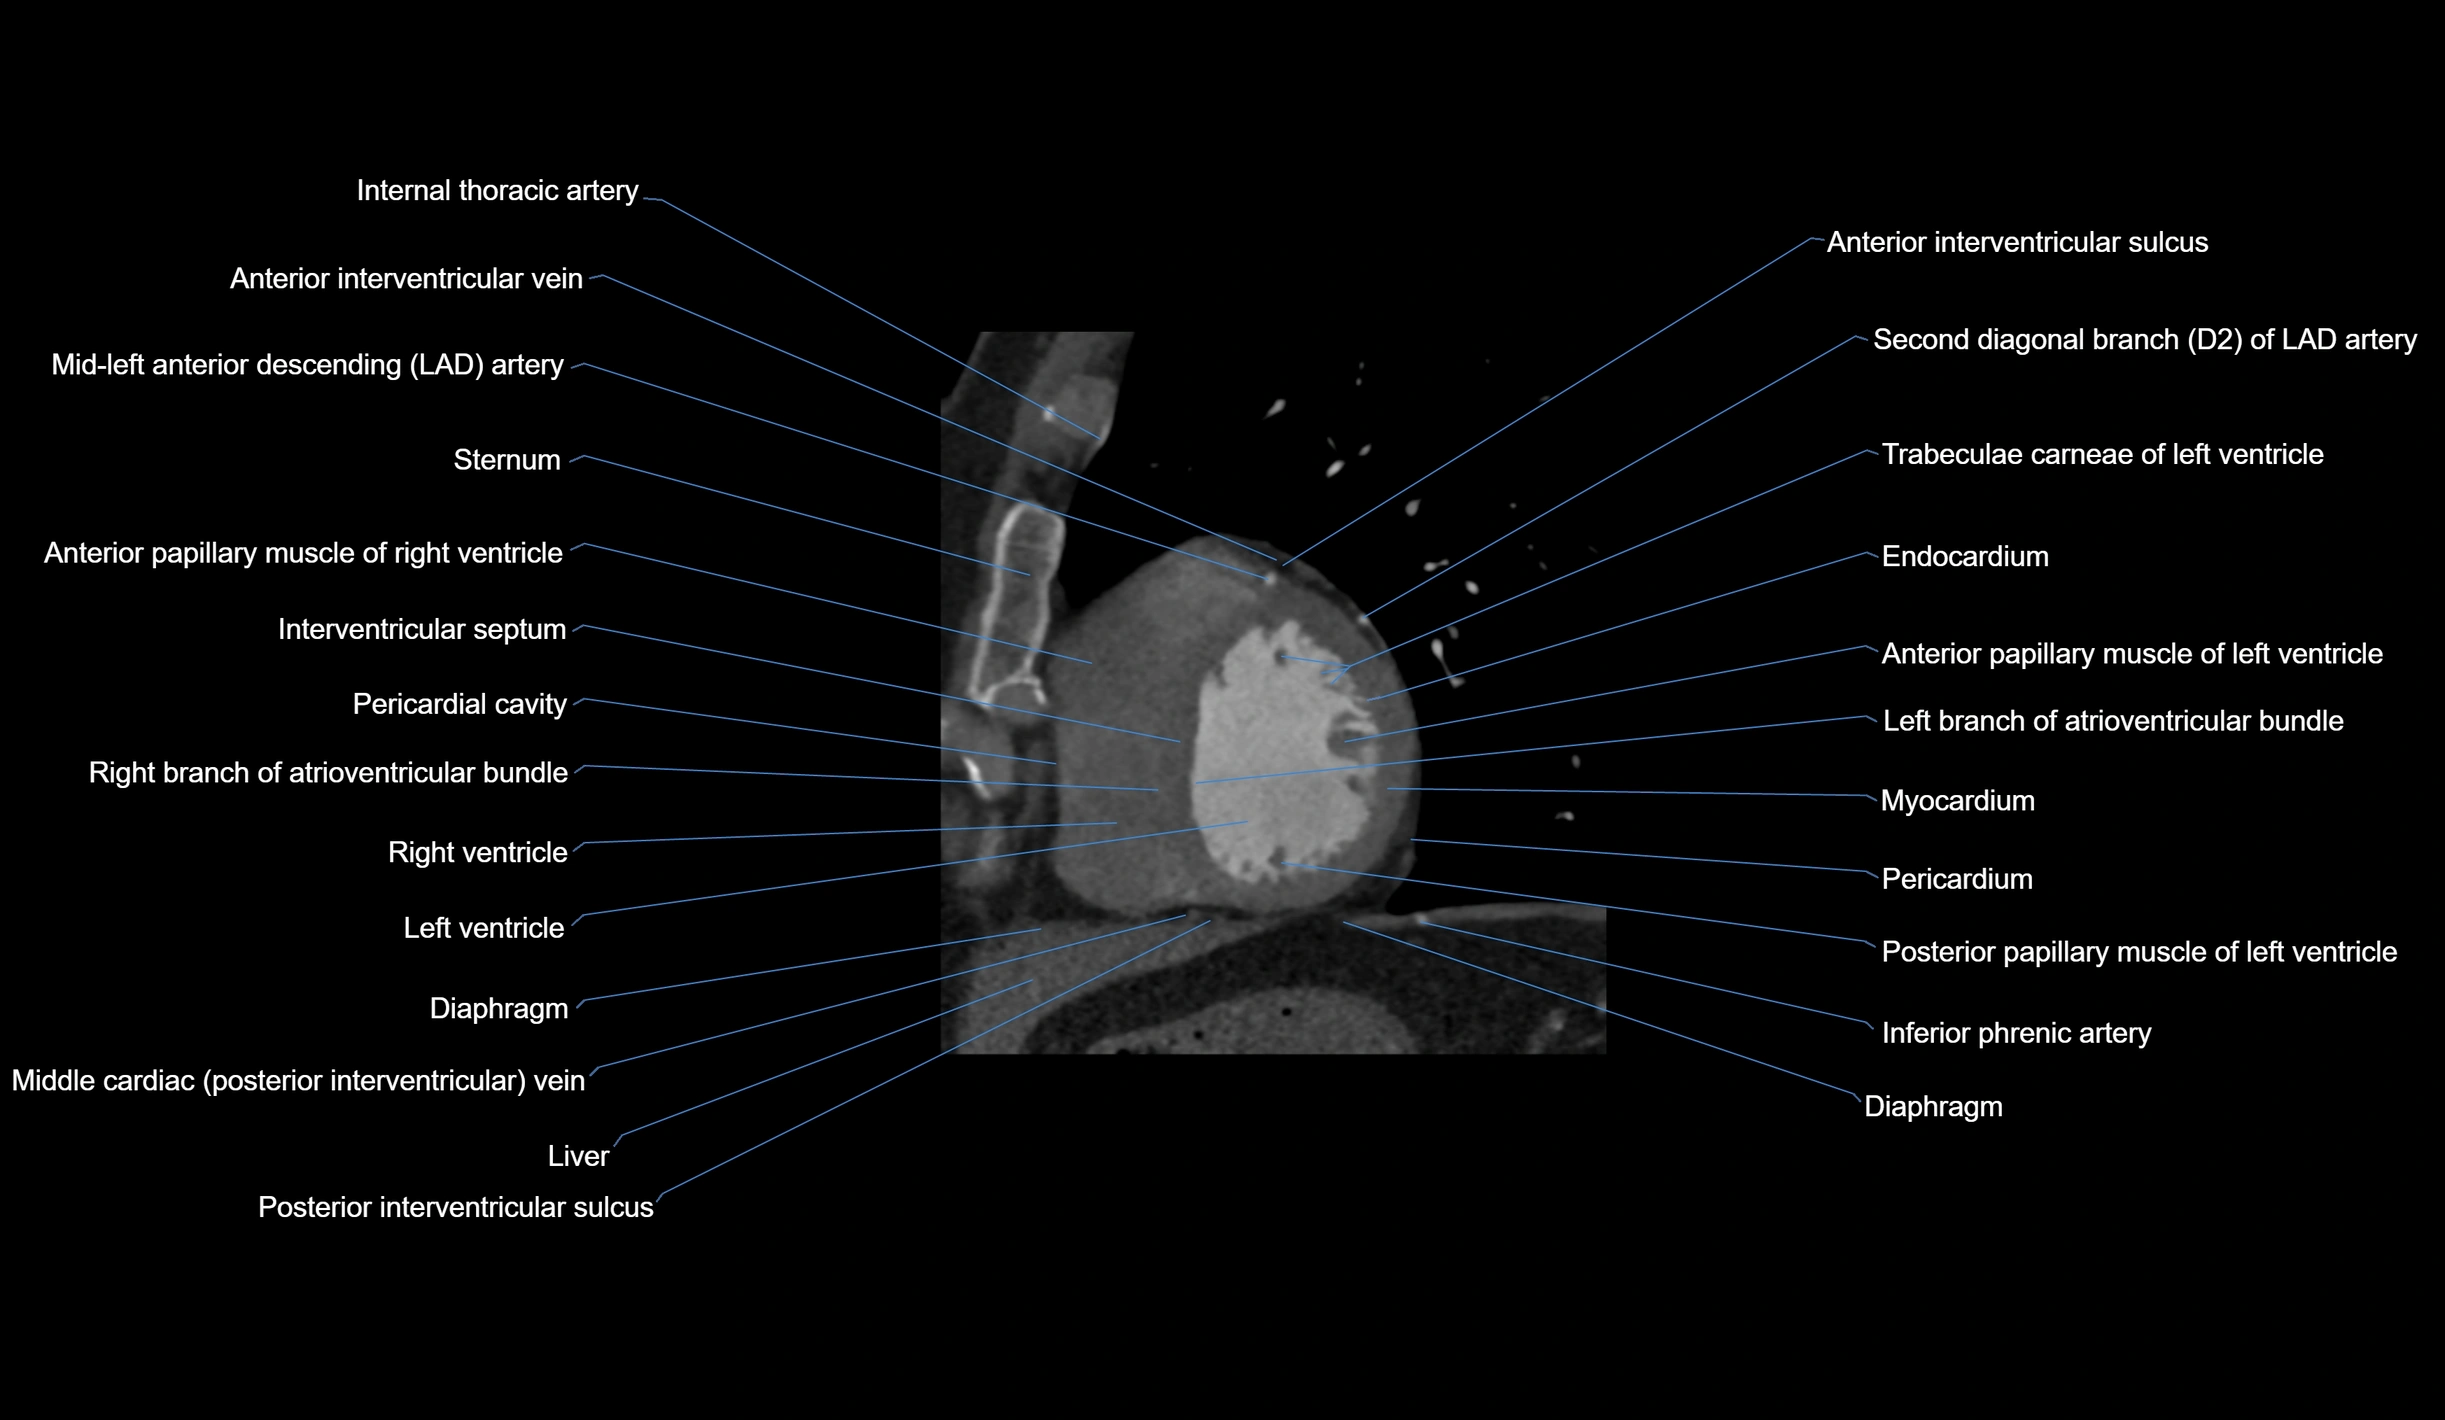

- Anterior interventricular sulcus

- Anterior papillary muscle

- Diaphragm

- Endocardium

- Interventricular Septum

- Left branch of atrioventricular bundle

- Myocardium

- Pericardial cavity

- Pericardium

- Posterior interventricular sulcus

- Posterior papillary muscle

- Right branch of atrioventricular bundle

- Second diagonal branch (D2) of LAD

- Trabeculae carneae